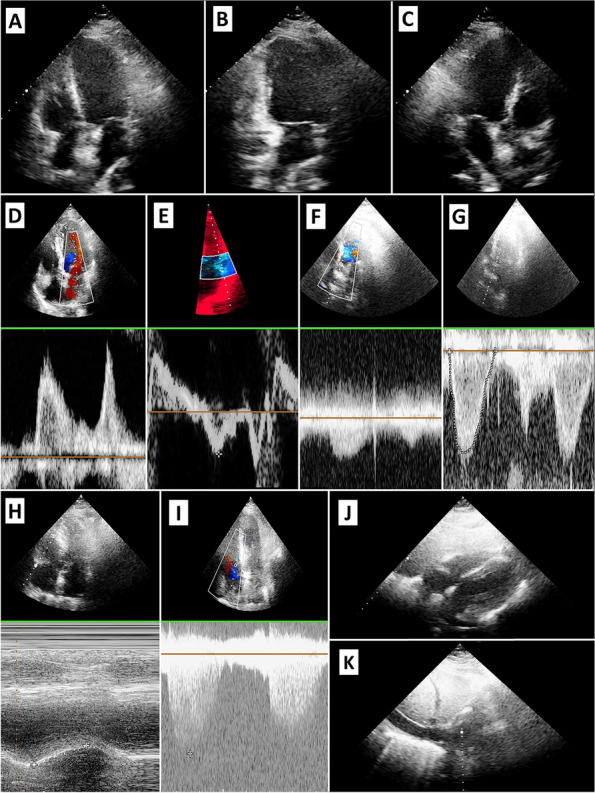

Aims: To evaluate the feasibility of a transthoracic echocardiogram using an apical-subcostal protocol in invasive mechanical ventilation (IMV) and prone position.

Methods: Prospective study of adults who required a prone position during IMV. A pillow was placed only under the left hemithorax in the prone position to elevate and ease the apical and subcostal windows. A critical care cardiologist (prone group) acquired and evaluated the images using the apical-subcostal protocol. Besides, we used ambulatory echocardiograms performed as a comparative group (supine group).

Results: 86 patients were included, 43 in the prone and 43 in the supine. In the prone group, the indication to perform an echocardiogram was hemodynamic monitoring. All patients were ventilated with protective parameters, and the mean end-expiratory pressure was 10.6 cmH2O. The protocol was performed entirely in 42 of 43 patients in the prone group because one patient did not have any acoustic window. In the 43 patients in the prone group analyzed and compared to the supine group, global biventricular function was assessed in 97.7% (p = 1.0), severe heart valve disease in 88.4% (p = 0.055), ruled out of the presence of pulmonary hypertension in 76.7% (p = 0.80), pericardial effusion in 93% (p = 0.12), and volume status by inferior vena cava in 93% (p = 0.48). Comparing prone versus supine position, a statistical difference was found when evaluating the left ventricle apical 2-chamber view (65.1 versus 100%, p < 0.01) and its segmental function (53.4 versus 100%, p < 0.01).

Conclusion: The echocardiogram using an apical-subcostal protocol is feasible in patients in the IMV and prone position.